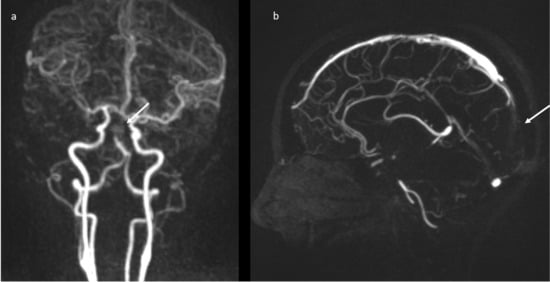

A brain computed tomography (CT) scan showed multiple subacute intra-axial hemorrhages in atypical locations, including the right frontal and the temporal lobes (Figure 1), with ipsilateral hemorrhagic subarachnoid suffusion, raising the suspicion of Labbè/superior longitudinal sinus thrombosis, even if brain angio-CT demonstrated only a non-occlusive thrombosis of the vein of Galen (Figure 2a), but also a floating thrombus within the aortic arch (Figure 2b).

Figure 2.

CT-angiography: partial thrombosis of the vein of Galen (a); presence of a floating thrombus within the aortic arch (b).

Brain magnetic resonance imaging (MRI) in the same day showed the presence of an acute basilar thrombosis (Figure 5a) associated with the superior sagittal sinus thrombosis (Figure 5b) with the delineation of hyperacute ischemic lesions in the vascular territory of the right posterior cerebral artery and of the perforating pontine branches (Figure 6).

Figure 5.

MR-angiography: acute basilar thrombosis associated with superior coronal (a) and sagittal (b) sinus thrombosis.